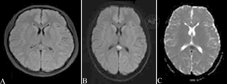

患者女性,20岁,因"发热伴头痛1 d"入院,头颅MRI示胼胝体压部结节状异常信号,液体衰减反转恢复序列呈稍高信号(A),弥散加权成像呈高信号(B),表观弥散系数图呈低信号(C)

病例5:女性,20岁,因"发热伴头痛1 d"入院。入院查体:血压108/63 mmHg,神志清楚,双侧瞳孔等大等圆,直径2.5 mm,对光反射灵敏,四肢肌力正常,脑膜刺激征阳性(颈部抵抗明显),病理反射未引出。常规检查:白细胞13.93×109/L,中性粒细胞89.9%,C反应蛋白16 mg/L。脑脊液:压力240 mmH2O(1 mmH2O=9.807 Pa),白细胞1 573×106/L,中性粒细胞90.3%,潘氏试验阳性,葡萄糖2.1 mmol/L,蛋白质856 mg/L,氯化物119 mmol/L。头颅MRI示胼胝体压部结节样异常影,T1低信号、T2高信号、FLAIR稍高信号、DWI高信号、ADC低信号(图5)。考虑化脓性脑膜炎引起PRES,给予抗感染、脱水降颅压等对症治疗后治愈出院。